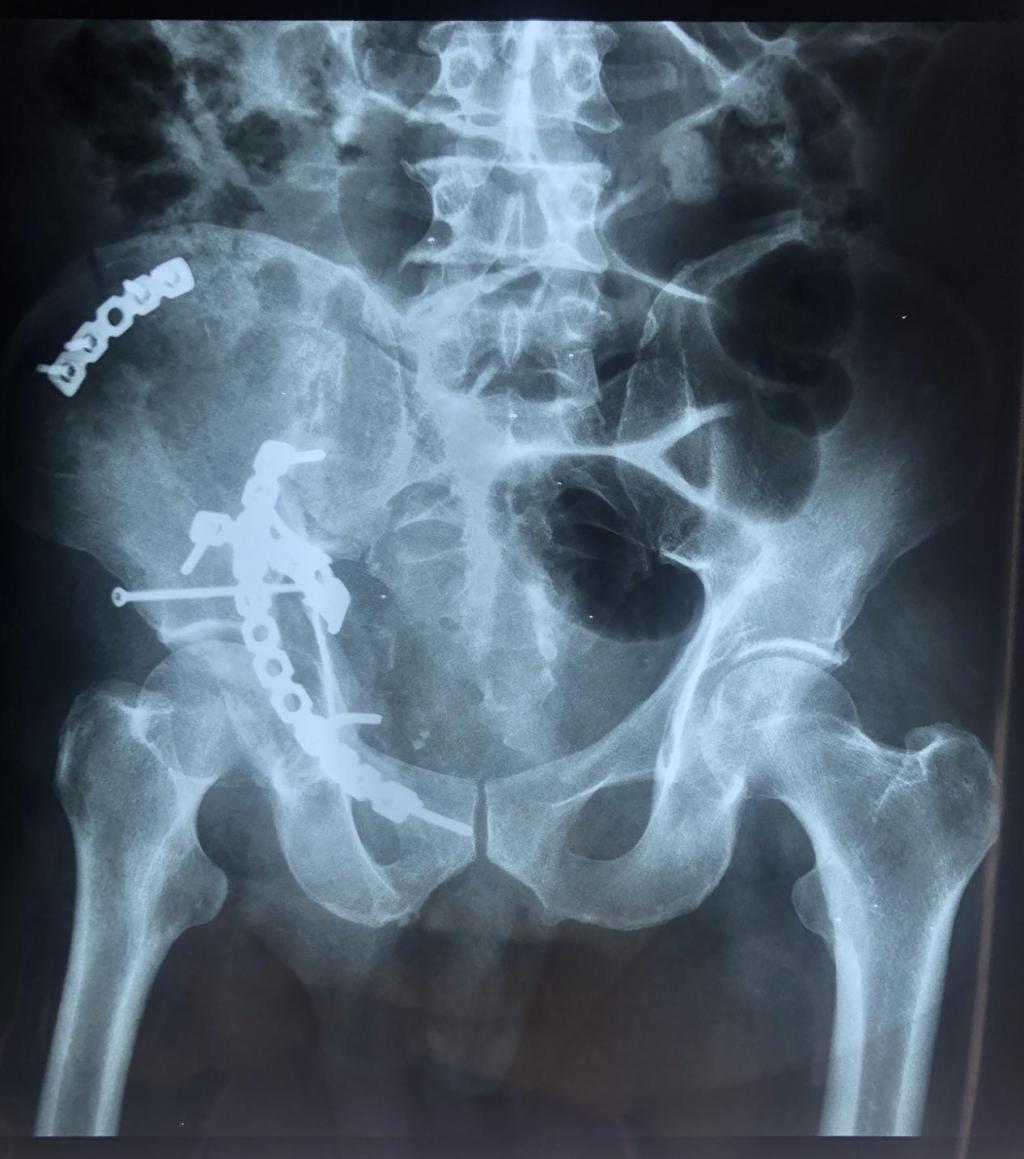

患者车祸致伤入院后,李玉民主任医师组织科内多次讨论认为,该患者为高能量损伤致复杂髋臼骨折,Letournel-Judet分型为高位前柱伴后半横骨折,股骨头中心脱位致臼顶、四方体粉碎性骨折,后柱横断向后方移位,前柱高位骨折伴旋转移位,头臼不匹配,臼内台阶明显,髋关节失去正常形态,失去明显的解剖标志,严重功能受限。须尽早积极手术治疗,否则后期出现畸形愈合关节功能丧失,股骨头坏死,致残率增高失去劳动能力。

经严谨的术前规划及方案设计,117号由郭宏军主任医师医疗组给予单一前方经腹直肌旁入路手术内固定。术后患者右髋关节功能恢复良好,自行翻身,半靠体位均不受限。

该患者伤后三周手术,骨折端已明显骨痂包绕,显露不易,术后给予高位前柱截骨使得髋臼骨折易于解剖复位固定,恢复了髋臼关节面光滑连续完整,头臼匹配良好,预防了股骨头后期坏死,使患者能够早期功能锻炼,最大程度减少了致残率,早日恢复劳动力。